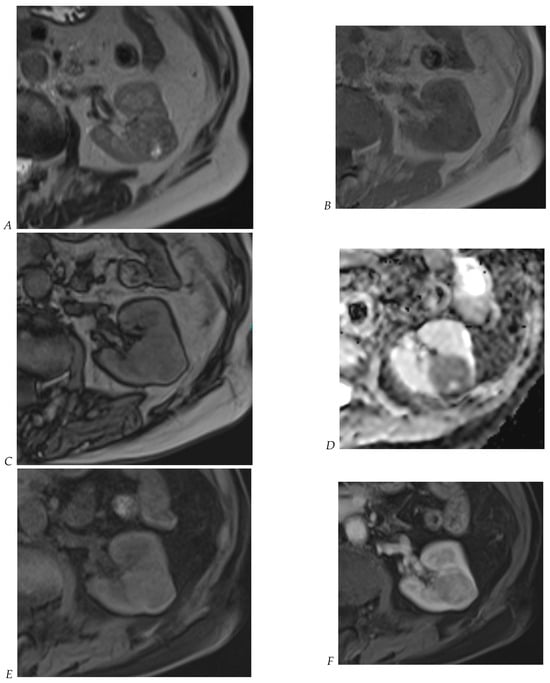

Figure 5.

Clear cell renal cell carcinoma in the right kidney of a 52-year-old-man. (A) Coronal T2-weighted fast SE image shows a large heterogeneous mass with areas of high signal intensity compared with renal parenchyma. Transverse in-phase (B,C) opposed-phase MR images show a subtle signal loss on the opposed-phase image. (D) The ADC map is heterogeneous with predominant areas of restriction of tumor diffusion. Transverse gadolinium-enhanced T1-weighted gradient-echo spoiled MR images in (E) corticomedullary, (F) nephrographic, (G) and delayed phase images show intense and rapid peripheral enhancement during the arterial and nephrographic phases followed by a rapid washout of contrast on the delayed phase. Central necrotic areas do not enhance. (H) Macroscopic view of the lesion after radical nephrectomy. The lesion appears heterogeneous. Courtesy of Pr S. Ferlicot, Department of Pathology, Bicêtre Hospital.